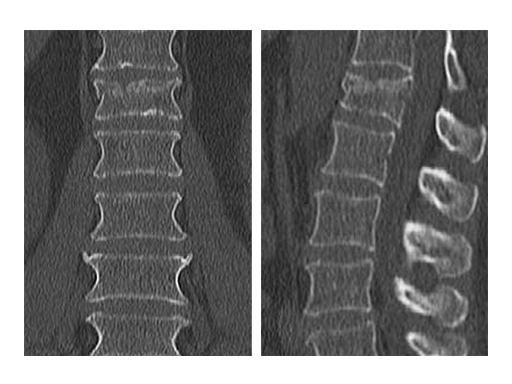

Follow up CT Scans (AP, lateral and coronal) after the second surgery.